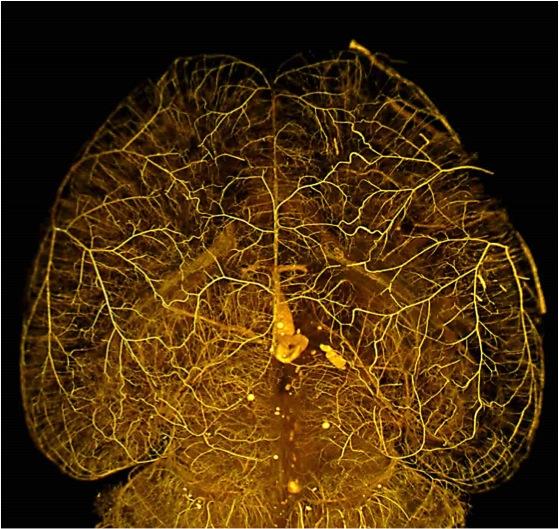

Scientists have known that when an artery is blocked, the damage to tissues downstream is often limited because these tissues continue to be nourished by special "collateral" vessels that connect the tissue to other arteries. However, for reasons that haven't been understood, the number and size of these collateral vessels - and thus the protection they afford - can vary greatly from one individual to the next. The UNC scientists have now implicated the Rabep2 gene as a major contributor to this variation in collateral vessel formation.

After this initial observation, Faber hypothesized that genetic differences might trigger these wide disparities in the extent of collaterals. Faber and colleagues began a tedious and lengthy search for the genetic factors responsible. They focused on collateral vessels in the brain, which are easier to image than in other tissues, and undertook experiments involving thousands of mice. By 2014, the group had narrowed the search to a small region on mouse chromosome 7, the variations of which accounted for nearly all of the differences in collateral development and tissue injury in the brains, hind limbs, and other tissues they examined.